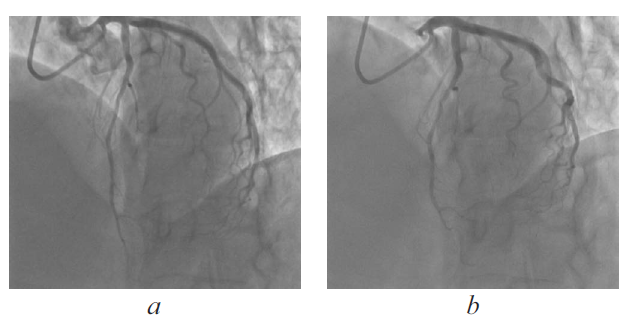

From March 18, 2014 to April 1, 2014, she was treated at a hospital in an emergency for suspected unstable angina. The patient underwent coronary angiography, which revealed a myocardial bridge of the left anterior descending artery with dynamic stenosis of up to 70%, and a small shunt from the pool of the left coronary artery into the left ventricle was revealed using contrast medium (Fig. 1 a, b). Coronary artery stenosis was not detected. On discharge, additional examinations, including Holter ECG monitoring and stress echocardiography, were recommended to the patient. Disaggregants (acetylsalicylic acid), calcium antagonists (amlodipine), diuretics (torasemide), ACE inhibitors, and beta-blockers were prescribed as components of a permanent medical treatment.

Fig. 1. Myocardial bridge of the left anterior descending artery (coronary angiography) diastole (a), systole (b)

Рис. 1. Мышечный мостик передней нисходящей артерии (коронарная ангиография) в диастолу (a) и в систолу (b)